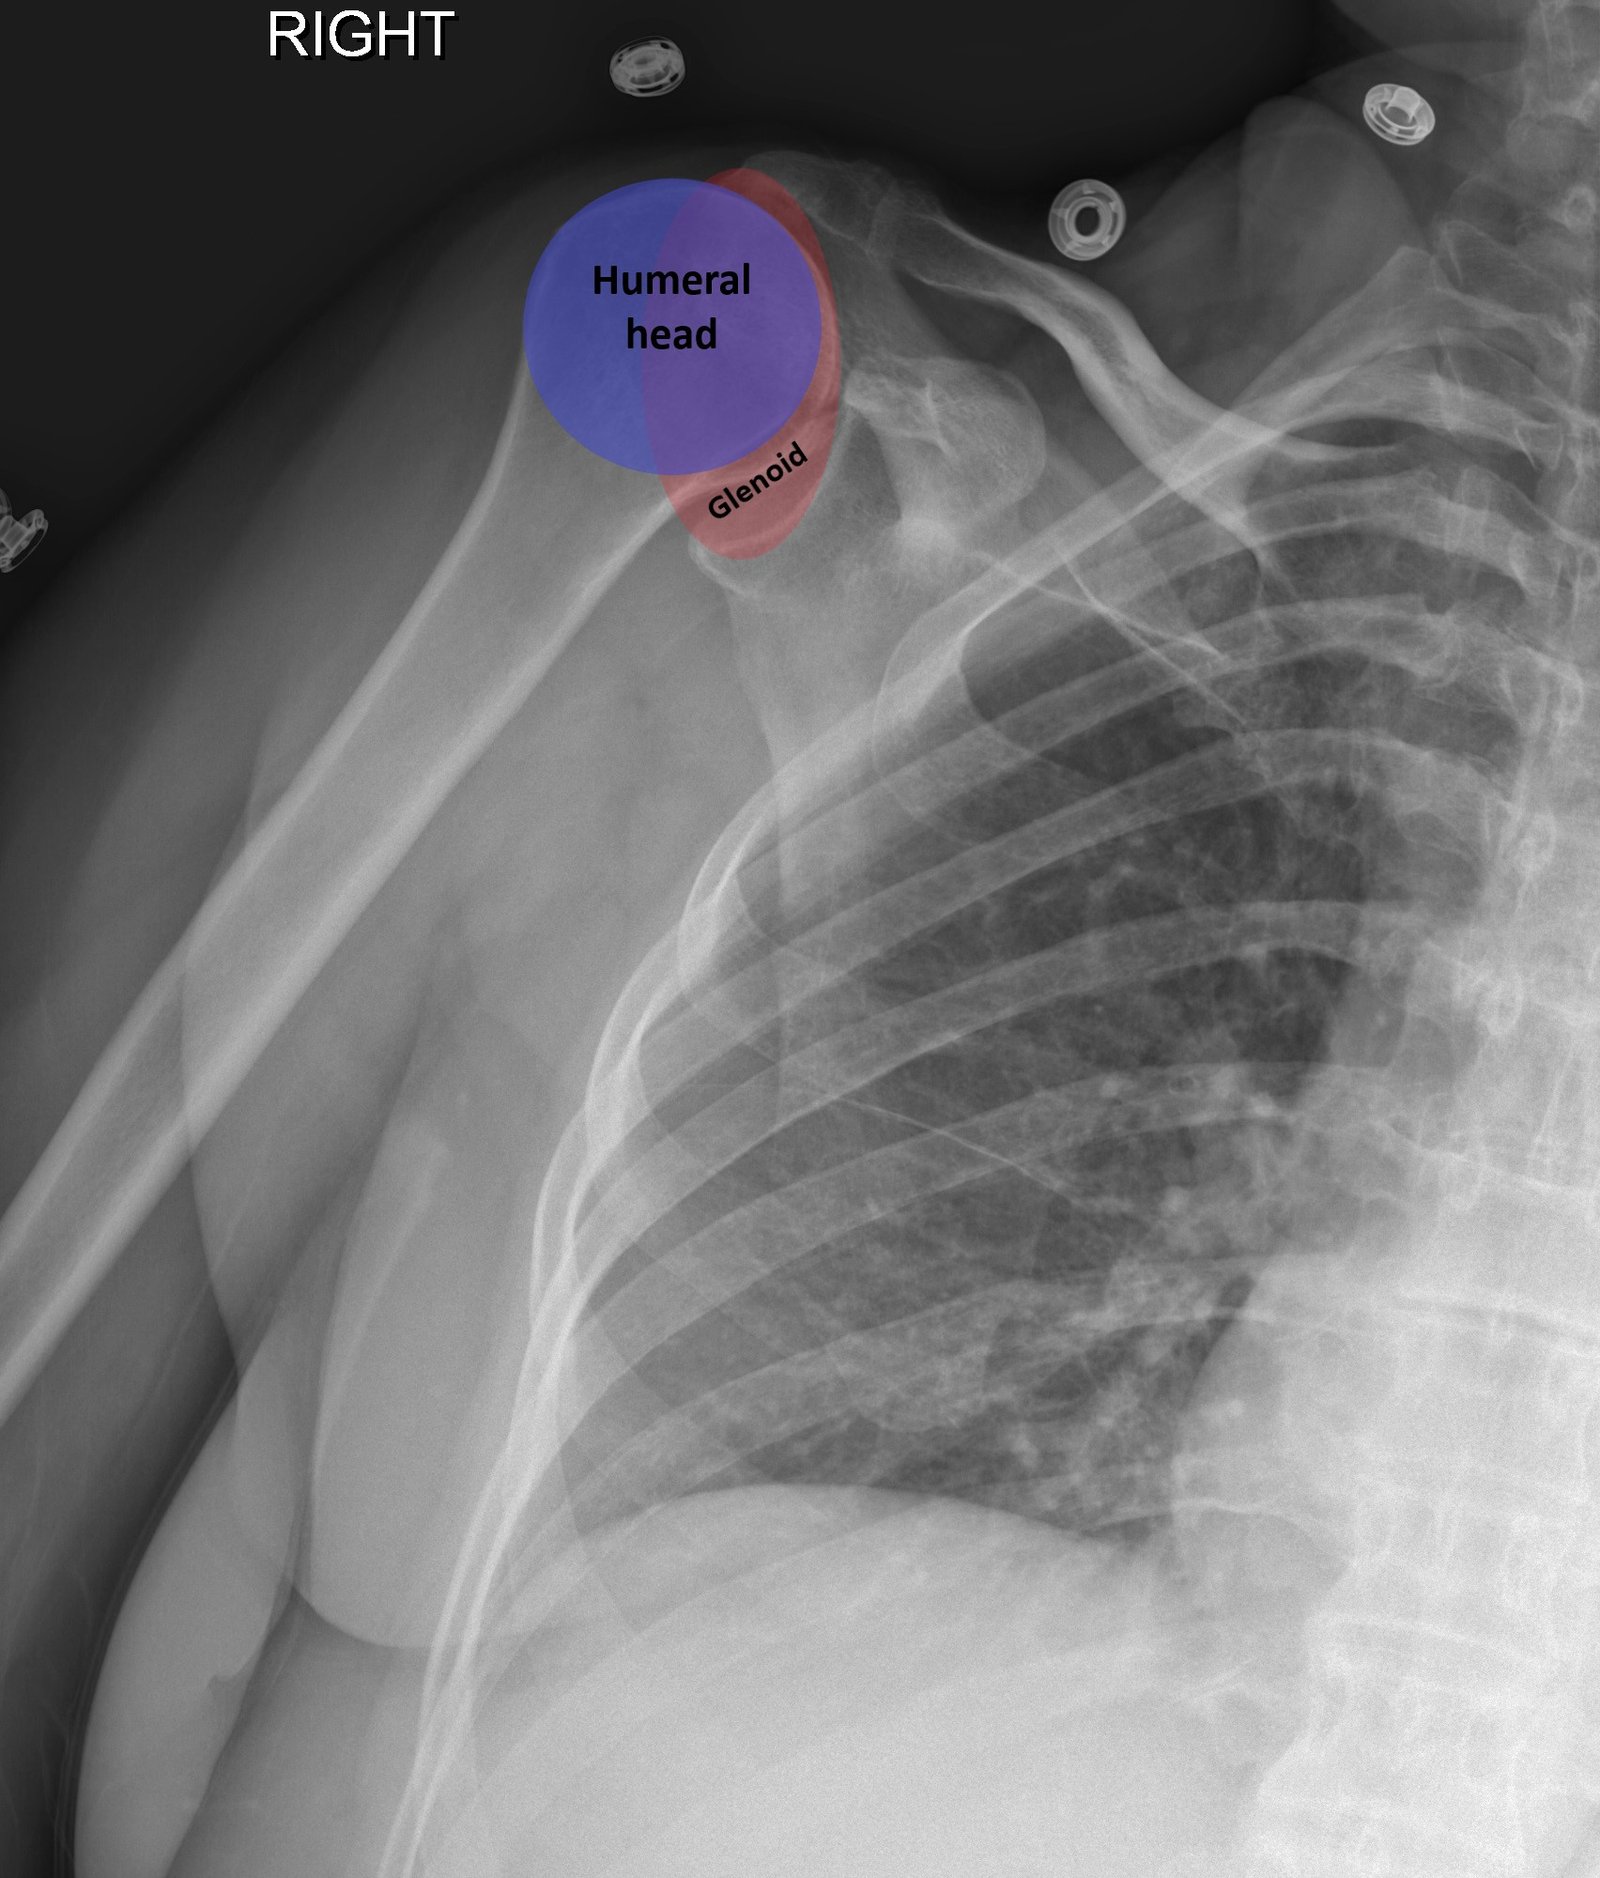

Bedside ultrasound with the transducer placed on the posterior right shoulder revealed an anterior dislocation of the right humerus. This is evident by displacement of the humeral head further away from the posteriorly placed ultrasound transducer, and appears deep to the glenoid cavity. In a posterior shoulder dislocation, the humeral head would appear closer to the transducer (and the near field of the ultrasound image) than the glenoid. Note that a hypoechoic, heterogeneous fluid collection is within the joint space, compatible with a hematoma. A right shoulder X-ray confirmed the anterior dislocation with no evidence of fracture. Under direct ultrasound guidance the glenohumeral joint space was injected with 10 mL of 2% lidocaine as an intraarticular anesthetic block. The right shoulder was reduced using continual traction. Post-reduction ultrasound demonstrated a successful shoulder reduction, depicted by the humeral head being relocated to its anatomical location, adjacent to the glenoid cavity, as noted on the ultrasound image. A hematoma remains present within the joint space. Successful shoulder reduction was further confirmed by X-ray. The patient’s arm was placed in a sling and she was discharged home with orthopedics follow-up.

Ultrasound guided intra-articular joint injections are best performed with the linear or curvilinear probe. With the probe on the patient’s lateral or posterior shoulder, locate the humeral head and the glenoid cavity. Determine the depth of the space and select a needle long enough to reach the cavity. Utilizing sterile technique, first place superficial local anesthetic. Then, advance the needle into the glenohumeral joint space and inject 10 to 20 mL of a local anesthetic, typically 1 or 2% plain lidocaine. An increase in anechoic space may be visible as the anesthetic is injected. The effect of the anesthetic should be active in about ten minutes.2,12